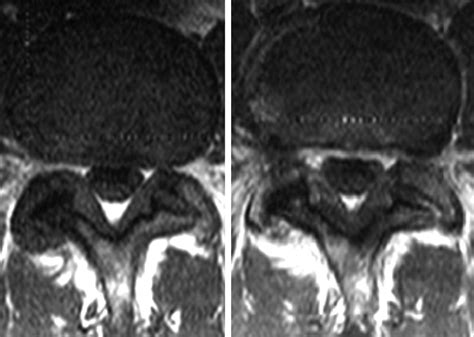

• Imaging studies: Diagnostic imaging, such as X-rays, MRI, or CT scans, can provide detailed images of the spine and identify the thickening of the ligamentum flavum.

Imaging studies are particularly important in confirming the diagnosis and determining the extent of the condition.